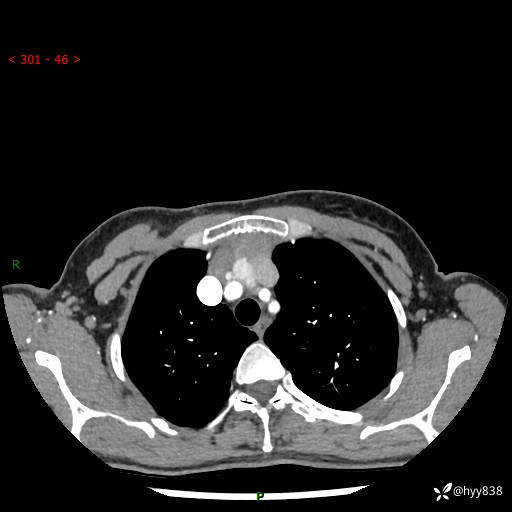

胸部CT平扫